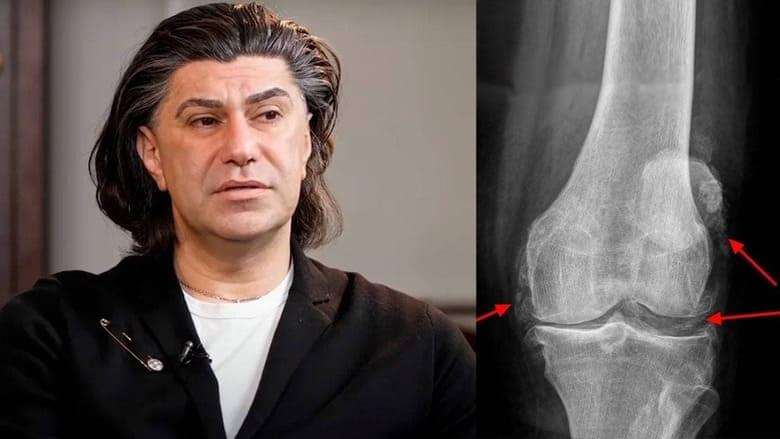

Uitați-vă la aceste imagini, puteți vedea că în imaginea din dreapta nu există spațiu articular, oasele se freacă unele de altele, provocând dureri puternice. Iar acest proces este foarte greu de oprit! În câțiva ani, persoana va deveni invalidă și nu se va mai putea servi singură.